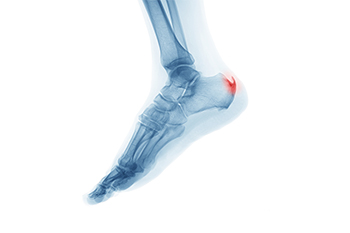

What Is a Heel Spur?

A heel spur is a bony growth that develops on the underside of the heel bone, often where the plantar fascia attaches. It typically forms over time as a response to ongoing stress or pressure on the foot. One of the main contributing factors is aging, as the tissues naturally lose elasticity and strength. Abnormal stress from repetitive activities, poor foot function, or walking patterns can place excessive strain on the heel. Carrying extra weight increases the load on the feet, which can lead to small tears in the plantar fascia. These micro-tears trigger inflammation and can encourage calcium deposits to build up, forming a spur. If you have heel pain, it is suggested that you schedule an appointment with a podiatrist who can accurately diagnose and treat heel spurs.

Heel spurs can be incredibly painful and sometimes may make you unable to participate in physical activities. To get medical care for your heel spurs, contact one of our podiatrists from APEX Foot & Ankle Center. Our doctors will do everything possible to treat your condition.

Heels Spurs

Heel spurs are formed by calcium deposits on the back of the foot where the heel is. This can also be caused by small fragments of bone breaking off one section of the foot, attaching onto the back of the foot. Heel spurs can also be bone growth on the back of the foot and may grow in the direction of the arch of the foot.

Older individuals usually suffer from heel spurs and pain sometimes intensifies with age. One of the main condition's spurs are related to is plantar fasciitis.

Pain

The pain associated with spurs is often because of weight placed on the feet. When someone is walking, their entire weight is concentrated on the feet. Bone spurs then have the tendency to affect other bones and tissues around the foot. As the pain continues, the feet will become tender and sensitive over time.

Treatments

There are many ways to treat heel spurs. If one is suffering from heel spurs in conjunction with pain, there are several methods for healing. Medication, surgery, and herbal care are some options.

Heel Spurs

Heel spurs are the result of calcium deposits that cause bony protrusions on the underside of the heel. Heel spurs are usually painless, but they have the potential to cause heel pain. Heel spurs tend to be associated with plantar fasciitis, which is a condition that causes inflammation of the band of connective tissue that runs along the bottom of the foot. They most often occur to athletes whose sports involve a lot of running and jumping.

Some risk factors for developing heel spurs include running and jogging on hard surfaces, being obese, wearing poorly fitting shoes, or having walking gait abnormalities.

It is possible to have a heel spur without showing signs of any symptoms. However, if inflammation develops at the point of the spur’s formation, you may have pain while walking or running. In terms of diagnosis, sometimes all a doctor needs to know is that the patient is experiencing a sharp pain localized to the heel to diagnose a heel spur. Other times, an x-ray may be needed to confirm the presence of a heel spur.

Heel spurs can be prevented by wearing well-fitting shoes that have shock-absorbent soles. You should also be sure that you are choosing the right shoe for the activity you want to partake in; for example, do not wear walking shoes when you want to go on a run. Additionally, maintaining a healthy weight can be beneficial toward preventing heel spurs, as it will prevent an excess amount of pressure being placed on the ligaments.

There are a variety of treatment options for people with heel spurs. Some of these include stretching exercises, physical therapy, shoe inserts, or taping and strapping to rest stressed muscles and tendons. If you have heel pain that lasts longer than a month, don’t hesitate to seek help from a podiatrist. Your doctor can help you determine which treatment option is best for you.